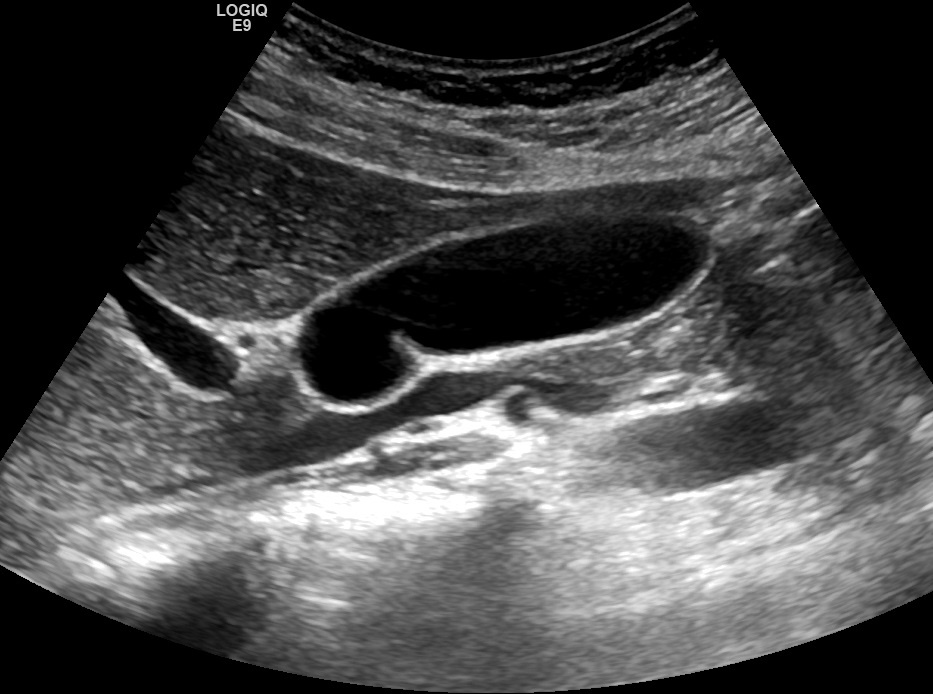

Рис. 01. Перегиб в шейке.

Видео 02. Перегиб в шейке